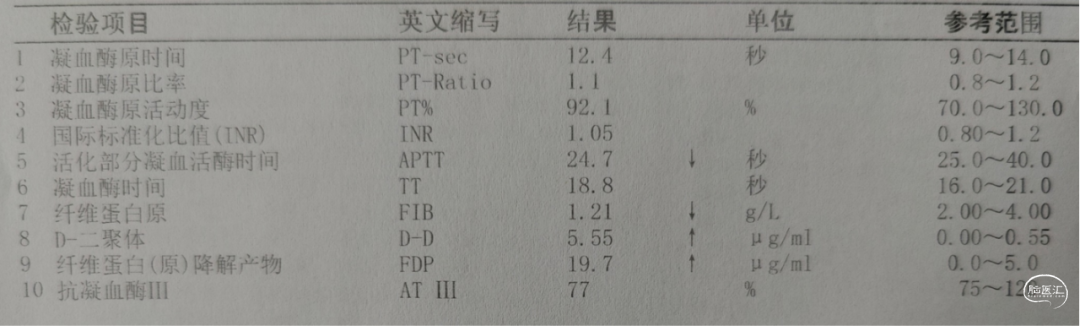

入院检查

![]()

入院化验

积极纠正凝血功能:氨甲环酸1g